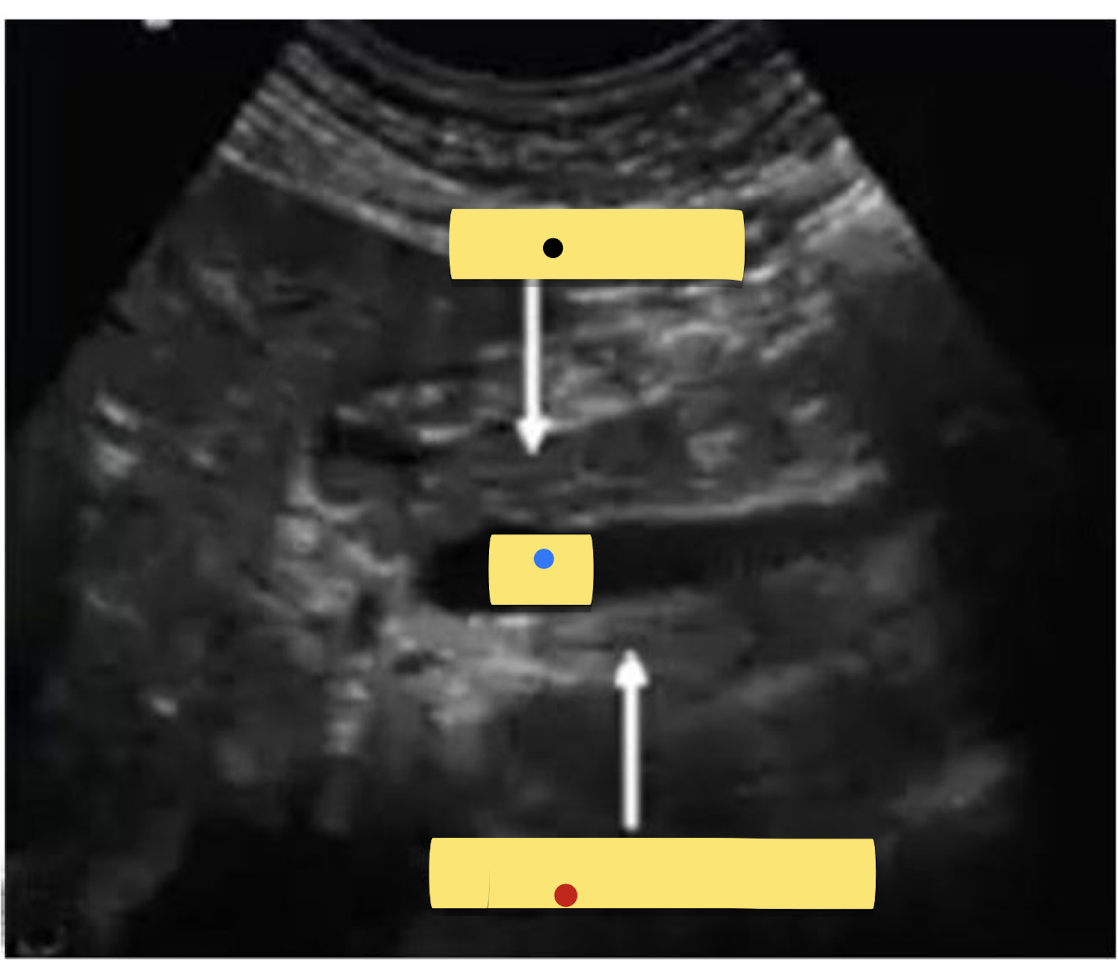

Label the Sagittal Image

Black = ?

Blue = ?

Red = ?

Black = Pancreatic Neck

Blue = SMV

Red = Uncinate Process